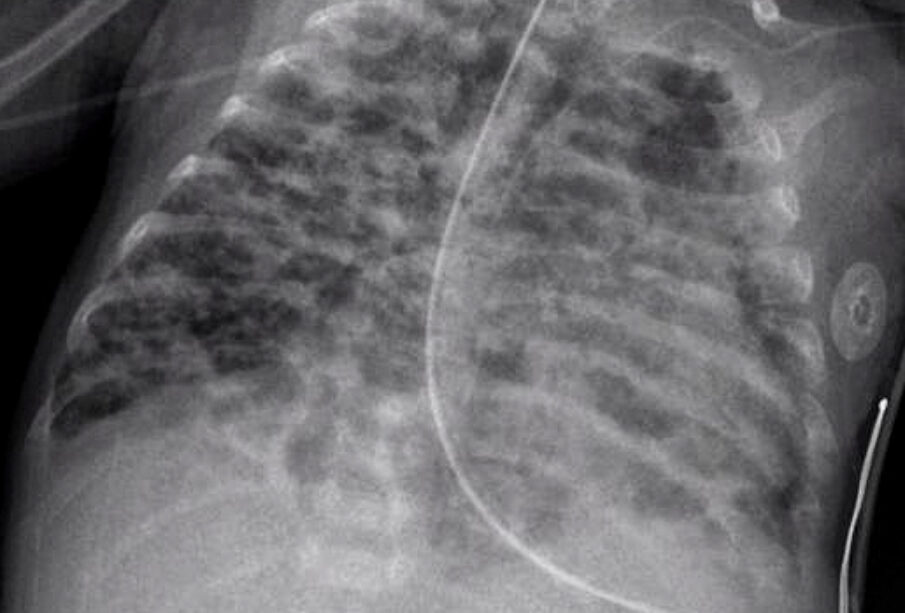

Η ιατρική απεικόνιση είναι καθοριστική για τη διάγνωση της βρογχοπνευμονικής δυσπλασίας. Ακτινογραφίες θώρακα και αξονική τομογραφία δείχνουν αλλοιώσεις στη δομή των πνευμόνων, όπως υπερδιάταση, σύμπτωση τμημάτων (ατελεκτασία) και ίνωση (ουλοποίηση του ιστού).